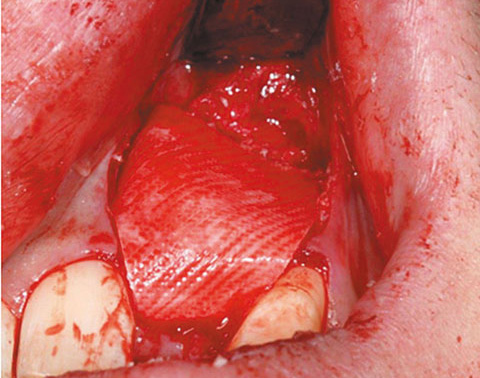

Ein lokaler dreidimensionaler Defekt würde normalerweise mit technikempfindlichen Knochenblöcken behandelt werden.

Durch die Verwendung einer OSSIX® Plus-Membran mit einer Titanschraube als stützender „Zeltstange“ (tent-pole) konnte Randelzhofer zeigen, dass sich derartige Defekte auch durch die Kombination mit partikulärem Knochenersatzmaterial regenerieren lassen.6

Behandlung eines ausgeprägten Knochendefekts in der ästhetischen Zone mit OSSIX® Plus-Membran auf einer Titanschraube als „Zeltstange“ und partikulärem Knochenersatzmaterial (li und Mi). Nach 5 Monaten war der Defekt optimal regeneriert, sowohl in vertikaler als auch in horizontaler Dimension (re).